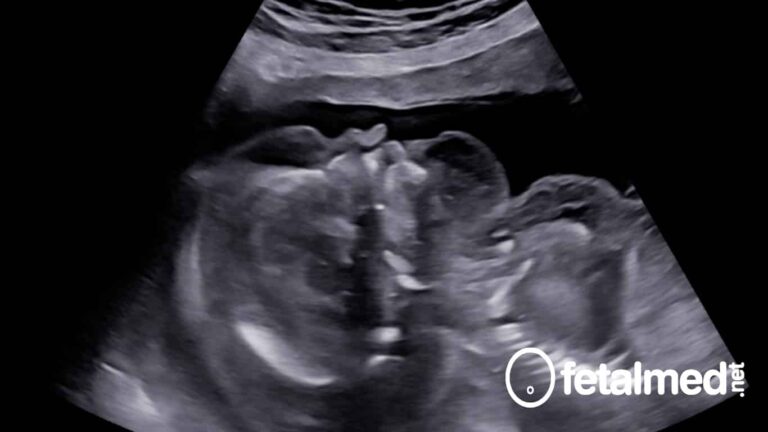

Hidropsia fetal: o que é e como tratar

Hidropsia fetal é uma condição grave onde o feto tem um acúmulo anormal de líquido em duas cavidades…

Escore cardiovascular na vigilância de fetos hidrópicos

A hidropsia fetal é uma doença grave do feto que está associada a uma alta mortalidade perinatal que…